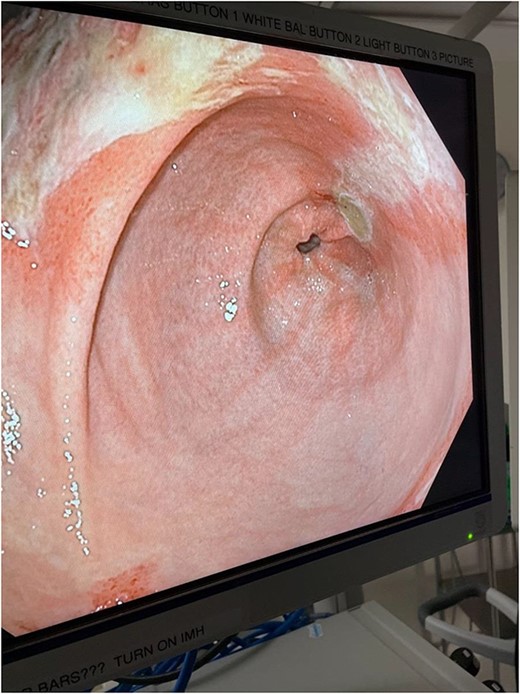

The decision was made to take the patient to the operating room. He underwent diagnostic laparoscopy, which showed a normal gastric antrum; however, on further inspection, a hemorrhagic and inflamed area of stomach was seen proximally at the fundus on the underside of the diaphragm. Next, esophagogastroduodenoscopy was performed, which demonstrated a large black necrotic area in the fundus (Fig. 3), as well as inflammation throughout the rest of the gastric body (Figs 4 and 5). At this point, malignancy could not be ruled out, so the operation was converted to open with a subxiphoid to supraumbilical midline incision. Once in the abdomen and able to further inspect the stomach, the frankly necrotic portion of fundus was noted to be adhered to the underside of the diaphragm and a contained purulent fluid collection was encountered in this area and drained. A partial gastrectomy was then undertaken in similar fashion to a sleeve gastrectomy. The lesser sac was entered and the stomach mobilized along the greater curvature with an energy device up through the short gastrics. A stapler was used to resect the entire necrotic portion of stomach from the midbody to the angle of His. Frozen sections were sent which were negative for malignancy. The remaining stomach was inspected for signs of malignancy, but none were found. For these reasons, no further resection was done. The entire staple line was imbricated due to concern for an ischemic etiology for the patient’s disease process, and two drains were left—one anterior and one posterior to the staple line. Final pathology showed prominent gangrenous necrosis, ulcer and acute necro-inflammatory exudate. Most of the specimen had no viable gastric mucosa, and no malignancy was found.

Intraoperative endoscopic image: inflammatory changes of gastric mucosa in midbody of stomach.

Intraoperative endoscopic image: inflammatory changes of gastric mucosa in antrum of stomach.